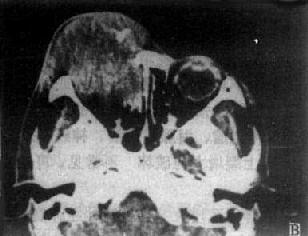

(一)眶内肿瘤 CT对确定眶内肿瘤的存在、位置、大小、范围和区别良性与恶性比较可靠。良性肿瘤表现为边缘清楚、光滑、密度均匀的高密度肿块(图5-2-2A)。而囊肿则为边缘清楚圆形低密度区。靠近眶壁时可出现凹窝,外围以硬化带。恶性肿瘤形态不规则,密度不均匀,边界也不清楚,常有眶骨破坏,并向颅内、鼻窦延伸。这些对恶性肿瘤的诊断有一定帮助。由鼻窦、颅内或眶骨肿瘤向眶内延伸,CT发现肿瘤主要部分在眶外,而眶内部分较小,有助于肿瘤起源的判断。对肿瘤病理性质的判断困难。

图5-2-2 眼眶CT扫描

左眼眶内血管瘤,肿瘤边缘清楚、光滑,均匀性显著强化

左眼眶内炎性假瘤,弥漫性,眼正常结构消失,伴眼球突出